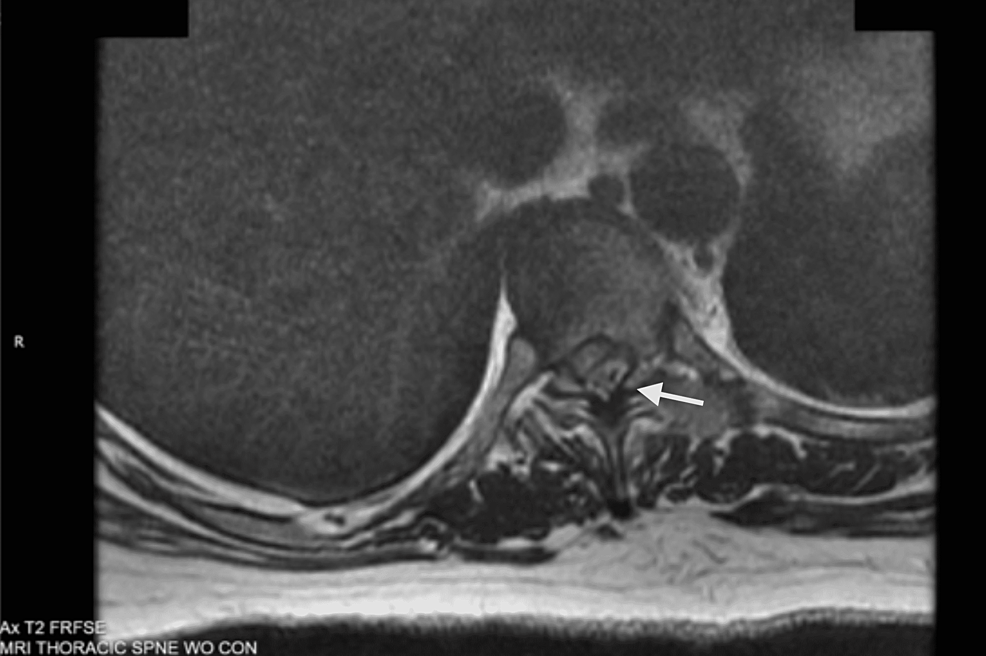

Cureus A Dorsal Epidural Herniated Disc Fragment Initially Presenting as GuillainBarré Syndrome Slipped Disc Epidural an epidural is a procedure that involves injecting a medication — either an anesthetic or a steroid — into the space around your. epidural steroid injections may help relieve sciatica pain from conditions like degenerated discs. when performed by a skilled healthcare provider, lumbar epidural steroid injections are an often effective and generally safe therapy option for. Slipped Disc Epidural.

Cureus A Dorsal Epidural Herniated Disc Fragment Initially Presenting as GuillainBarré Syndrome Slipped Disc Epidural an epidural is a procedure that involves injecting a medication — either an anesthetic or a steroid — into the space around your. It’s one of the most common causes of neck, back. an epidural steroid injection is used to relieve pain and inflammation in the spine. a herniated disk is also known as a slipped, ruptured. Slipped Disc Epidural.